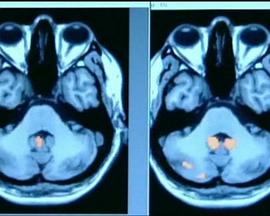

本部纪录片是BBC地平线系列推出的一档揭秘人类独特能力“记忆”的纪录片。如果你认为这种在我们日常生活中习以为常的能力,生来就是为了帮你记住东西的话,那么你就大错特错了。的确,记忆保存了生活的每一个细节,它塑造了属于个体独有的身份标示。然而这种本应在你的生命历程中,最值得称道和得以开发的能力,却被关注的程度最少。

在本期《地平线》节目中,你将踏上一次遨游在人类记忆中的非凡旅程。记忆看上去很简单,我们都会,就像呼吸一样。本片就将揭开这层表象,把这人类独有的神奇能力“记忆”的复杂呈现在你的面前。从一位试图通过药物抹去外伤性受损记忆的女士,到一位丧失记忆功能的男士,你将会看到一系列特异的个案。这些非凡故事,可能会改变你对这个人类独有能力的理解。结论揭示了这个令人震惊的事实:每个人和他自己的记忆没有丝毫差别,记忆就是自我。